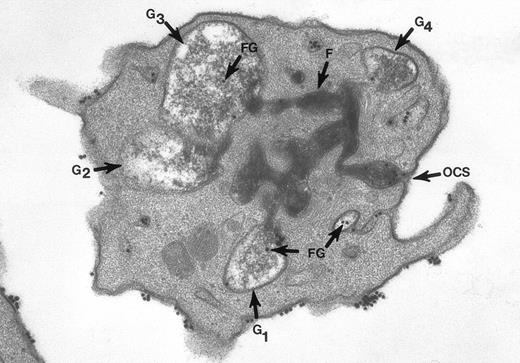

The surface and OCS membranes are the only structures stained by osmium black in resting platelets. After exposure to thrombin, the dense stain also enters α granules that have become labelized and communicate with the OCS.20 Fibrinogen and fibrin in the process of extrusion from α granules fill channels of the OCS. During this process the OCS becomes dilated, as do the labelized α granules, yielding the appearance of swollen vacuoles (Fig 2). In experiments where the platelets were combined with fibrinogen-coated gold particles before exposure to thrombin and fixation through the tannic acid staining procedure, Fgn/Au was present in OCS channels and in swollen α granules. The findings showed that the OCS is a two-way street, and α granules communicate with channels of the OCS to secrete their contents.

Thin section of a platelet from a sample of washed cells incubated with Fgn/Au particles for 15 minutes, then exposed to 5 U/mL of thrombin for 60 seconds before fixation in glutaraldehyde-tannic acid-osmium to selectively stain the platelet glycocalyx, fibrinogen, and fibrin. This example is one of several serial sections through the same platelet. It and the other serial sections show the typical features of shape change and internal transformation caused by thrombin. Fgn/Au particles are bound to the irregular surface and are in the process of entering channels of the OCS. The OCS channel indicated by an arrow (↑) is filled with fibrinogen and fibrin stained by tannic acid-osmium black. The tortuous channel is connected directly to several granules (G1, G2, G3) in various stages of labelization. Residual fibrinogen is stained by the reaction product. Fgn/Au particles carried by the OCS have entered the granules (G1, G3, G4). The direct connections between OCS channels and granules in this example and its serial sections is indisputable. Original magnification ×45,000. (Reprinted with permission.19)